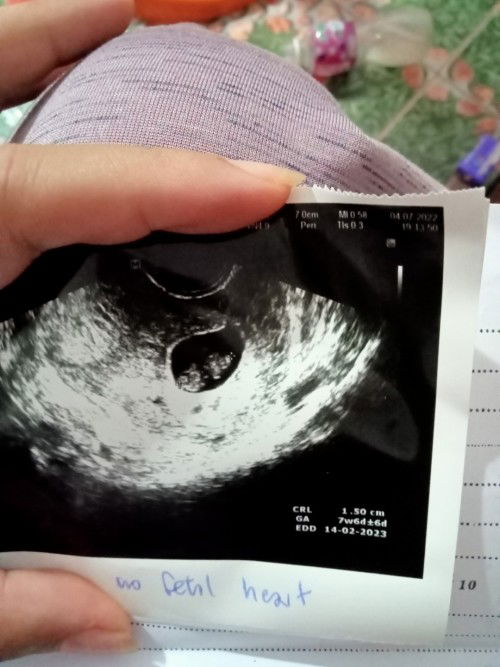

ใคร7วิคแล้วยังไม่เห็นหัวใจน้องบ้างค่ะ...พอดีบ้านนี้ไปซาวด์มาเห็นตัวน้องโตขึ้นแต่ไม่เห็นหัวใจน้องหมอลงนัดยุติการตั้งครรภ์วันที่11นี้ค่ะกังวลไปหมดน้องจากเราไปจริงๆหรอใครมี ประสบการณ์แบบนี้บ้างคะช่วยแนะนำหน่อย..ขอบคุณค่ะ